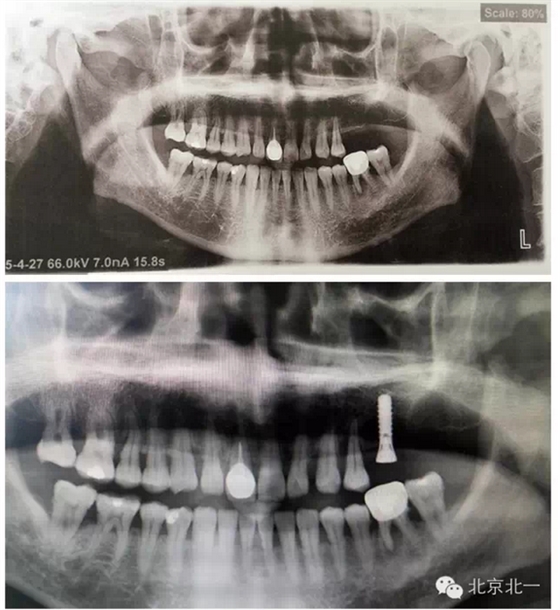

7 植體備份不合理,無備骨粉骨膜,術(shù)中情況特殊,需要植骨蓋膜。(圖七、手術(shù)沒有PLAN

B計(jì)劃,無骨粉骨膜,無大一號(hào)種植體,,有CBCT,拔牙后已經(jīng)2年,打開后拔牙窩沒有愈合,要植骨有木有,只能放棄一顆植入,等待下一次了)